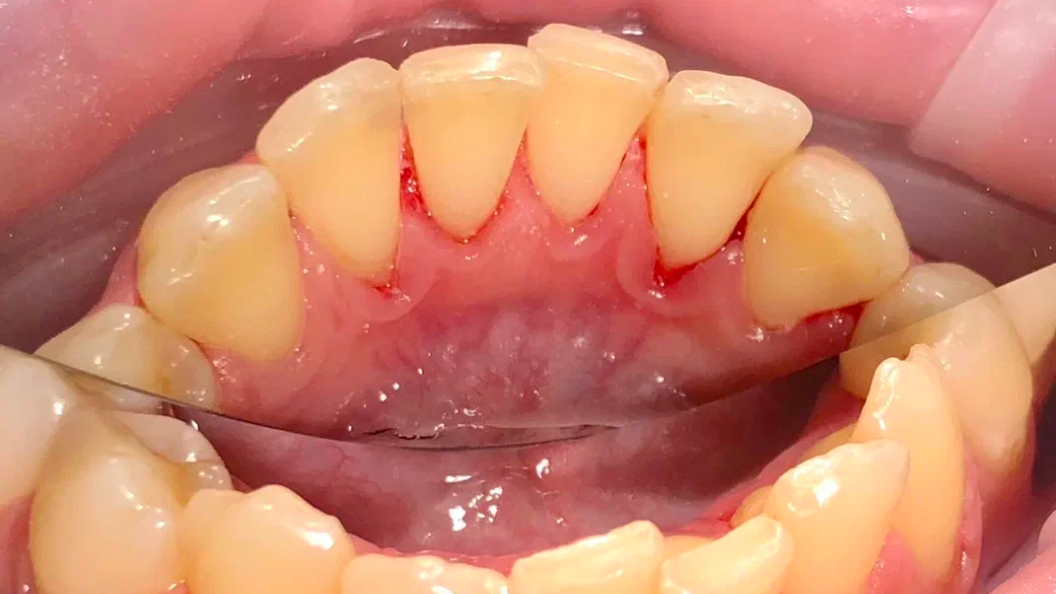

До и после лечения

В «Стоматологию Комфорта» обратился пациент с жалобами на наличие зубных отложений, а также кровоточивость дёсен во время чистки зубов. Врач Луцюк Наталья Владимировна провела осмотр и диагностировала хронический катаральный генерализованный гингивит. Было принято решение о проведении профессиональной гигиены полости рта с целью снятия минерализованных зубных отложений ультразвуком и удаления пигментированного налета пескоструйным аппаратом, а также последующей полировкой щеткой с пастой SuperPolish.

В ходе лечения проведены следующие работы:

- снятие минерализованных зубных отложений ультразвуком;

- удаление пигментированного налёта пескоструйным аппаратом;

- полировка зубов резиновой насадкой;

- финальная полировка пастой SuperPolish.